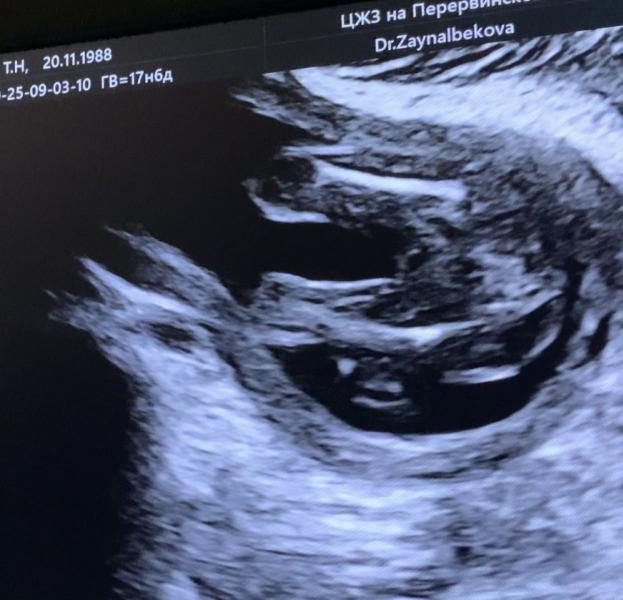

Тема пола не закрыта😂

Кого вы видите на первом фото? А на втором?😅

Срок на узи ровно 19 недель (по первому скринингу) разница в фото несколько секунд

На первом фото видно половые губы , на втором видно мальчика 🤣

Очертания писюна и мошонки на обоих )